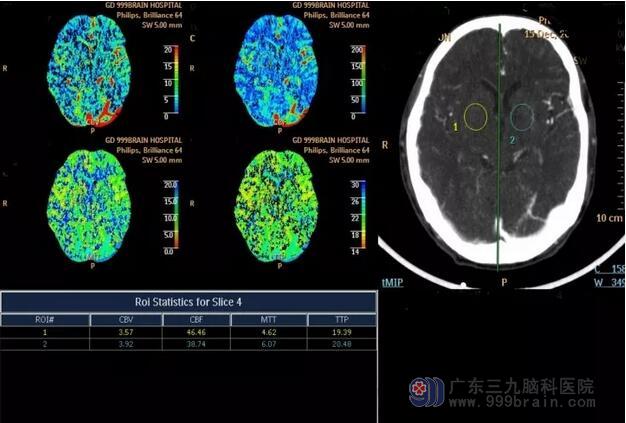

送到我院之后,神经内一科王玉周副主任医师根据钟叔表现出的临床症状与病历资料,并结合入院后MR灌注成像与脑血管造影等检查结果,即判断钟叔为颅脑血流低灌注引起的轻型卒中复发。在这种情况下,王玉周副主任医生为钟叔制定了以恢复血流灌注,改善脑循环为主的治疗方案,以尽可能的改善钟叔的预后情况。

我院MR灌注成像(术前)

经过一番紧张有序的手术治疗,最后成功实现对颈内动脉狭窄处的扩张。通过对比术前、术后的造影影像,可以见到狭窄处得到明显改善,而且MR灌注成像也证实了颅脑已经恢复供血灌注,这对改善钟叔的预后起了重要作用。

我院MR灌注成像(术后)